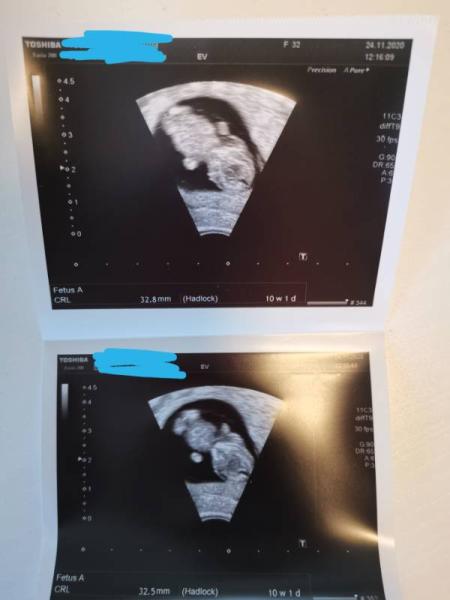

Hallo ihr lieben. Ich war heute auch wieder beim Ultraschall und unserer kleinen Erdnuss gehts Prima. Hat umhergeturnt und war total aktiv Bin heute bei 9+6 und hab meinen Mutter Kind Pass bekommen Meine FA hat mir heute gesagt das sie mich mit der 15. SSW in die Frühkarenz schicken wird da ich letztes Jahr eine ziemlich schwere Konisation hatte. Da ich aber sowieso zu Hause bin macht das nichts. Anbei noch das neue Ultraschallbild... Ich finde es sieht aus wie eine kleine Schildkröte

Bild zu 2. Ultraschall - Forum für Juni - Mamis